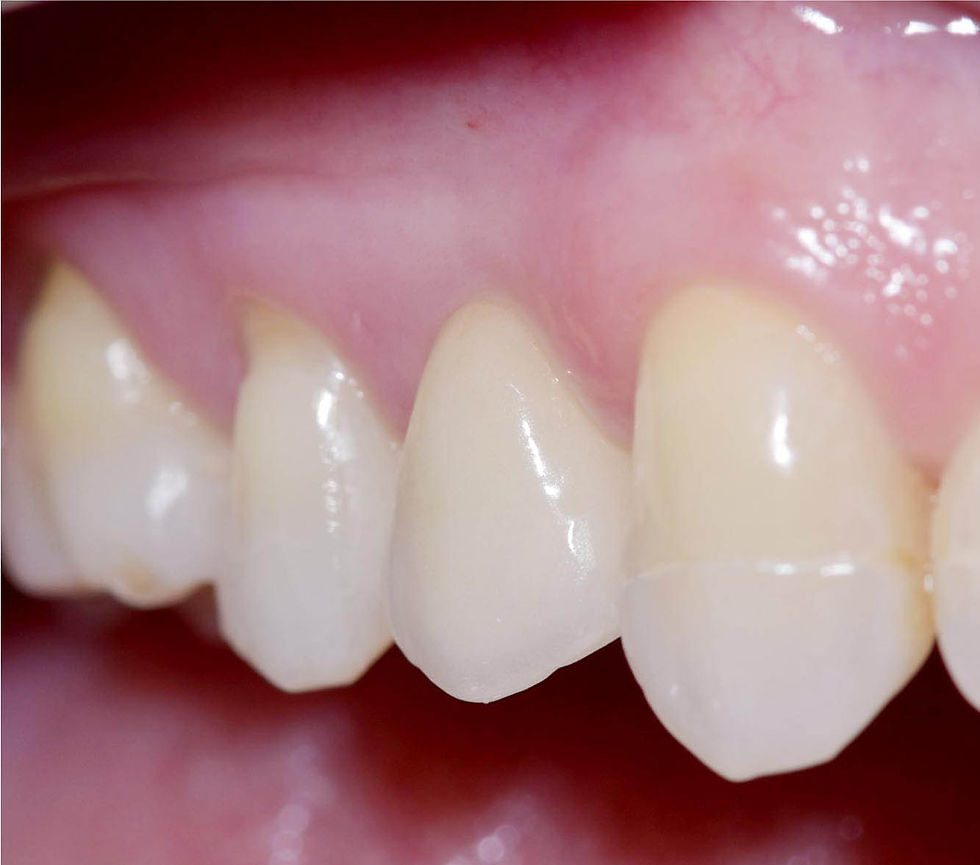

Two years follow up clinical images.